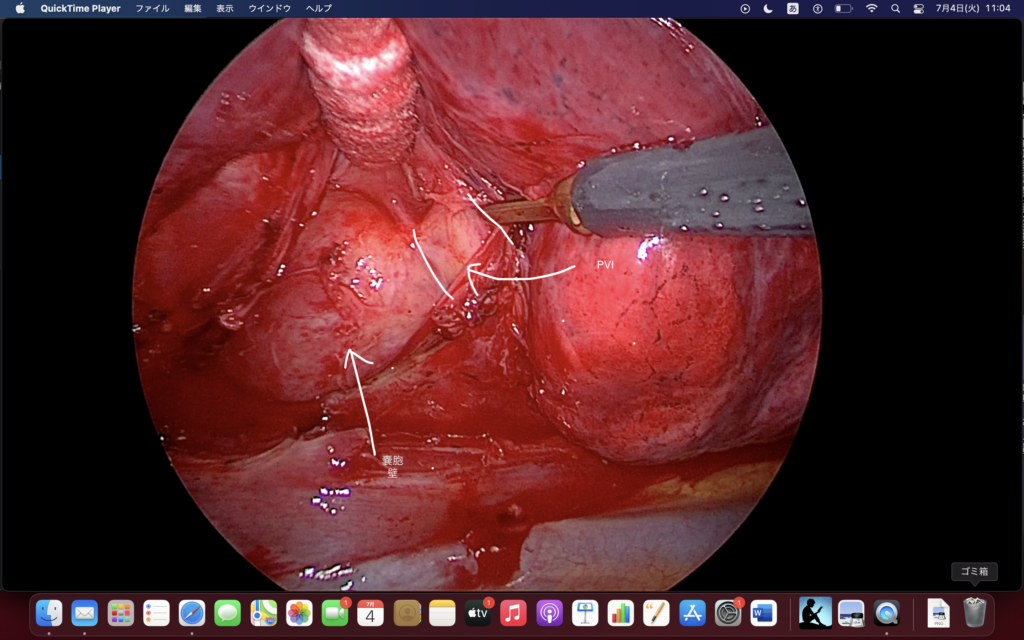

結局、何が大事かっていうと、嚢胞がどこまで広がってるかわからんもんで、

「知っているものを出していく」ことが重要になる。

それを如何(どう)達成するか。

PVIやるときはこっとん2本て相場が決まってんのかな?

肺門(の縦隔)は心膜より頭側だから、PVはすくなくとも心膜より頭側にきまってるんだけど。

嚢胞で抑えることになるから、っていう話で。

3者(A, B, V)との関係をつねに意識してください。